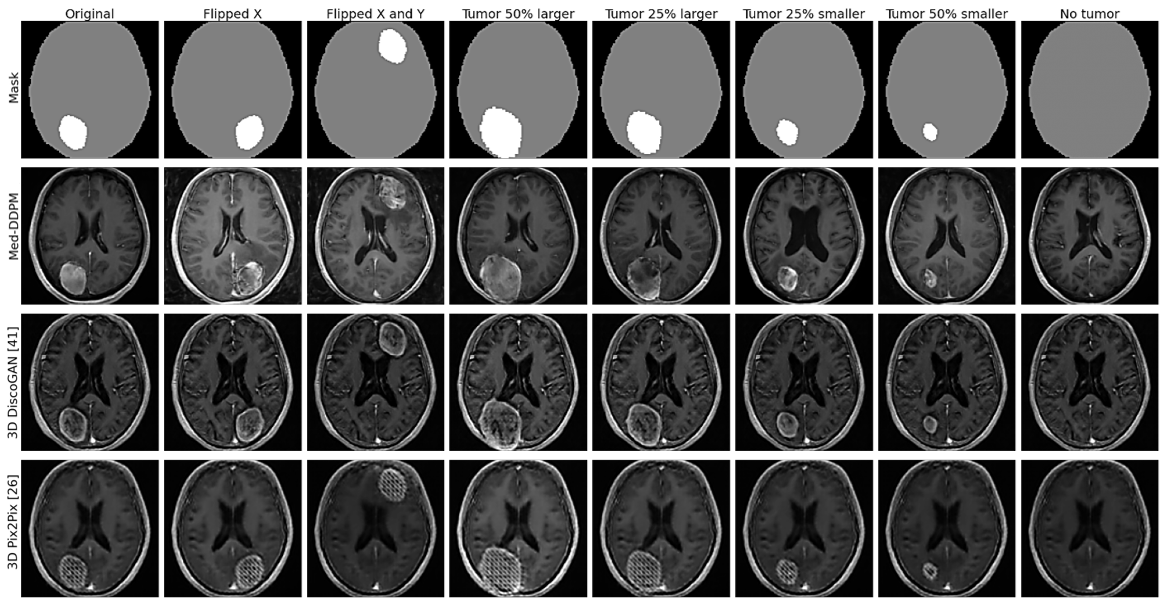

Fig.3 offers a closer look at tumor areas in axial plane images, comparing real and synthetic images from Med-DDPM and two other conditional GAN models. Fig.4 features synthetic images created using manipulated masks, which are generated by two different functions. The first function scales tumor masks from their center, while the second shifts them within the brain in axial, coronal, and sagittal planes. Fig. 5 demonstrates the variety of synthetic images produced from a single input mask. The Pix2Pix model often yields blurry images, especially with unseen test masks. DiscoGAN performs better, producing more realistic images with distinct tumor areas. However, DiscoGAN’s images lack clear brain features and exhibit coarse gyri and sulci.

In contrast, our Med-DDPM model excels in generating highly realistic and detailed images. It captures both brain features and tumor regions clearly, though occasionally it shows incomplete tumor ring enhancement, similar to real images. The peri-tumoral edema rendered by Med-DDPM appears more realistic than the isotropic low-intensity output of DiscoGAN, making these synthesized images closely resemble real ones.